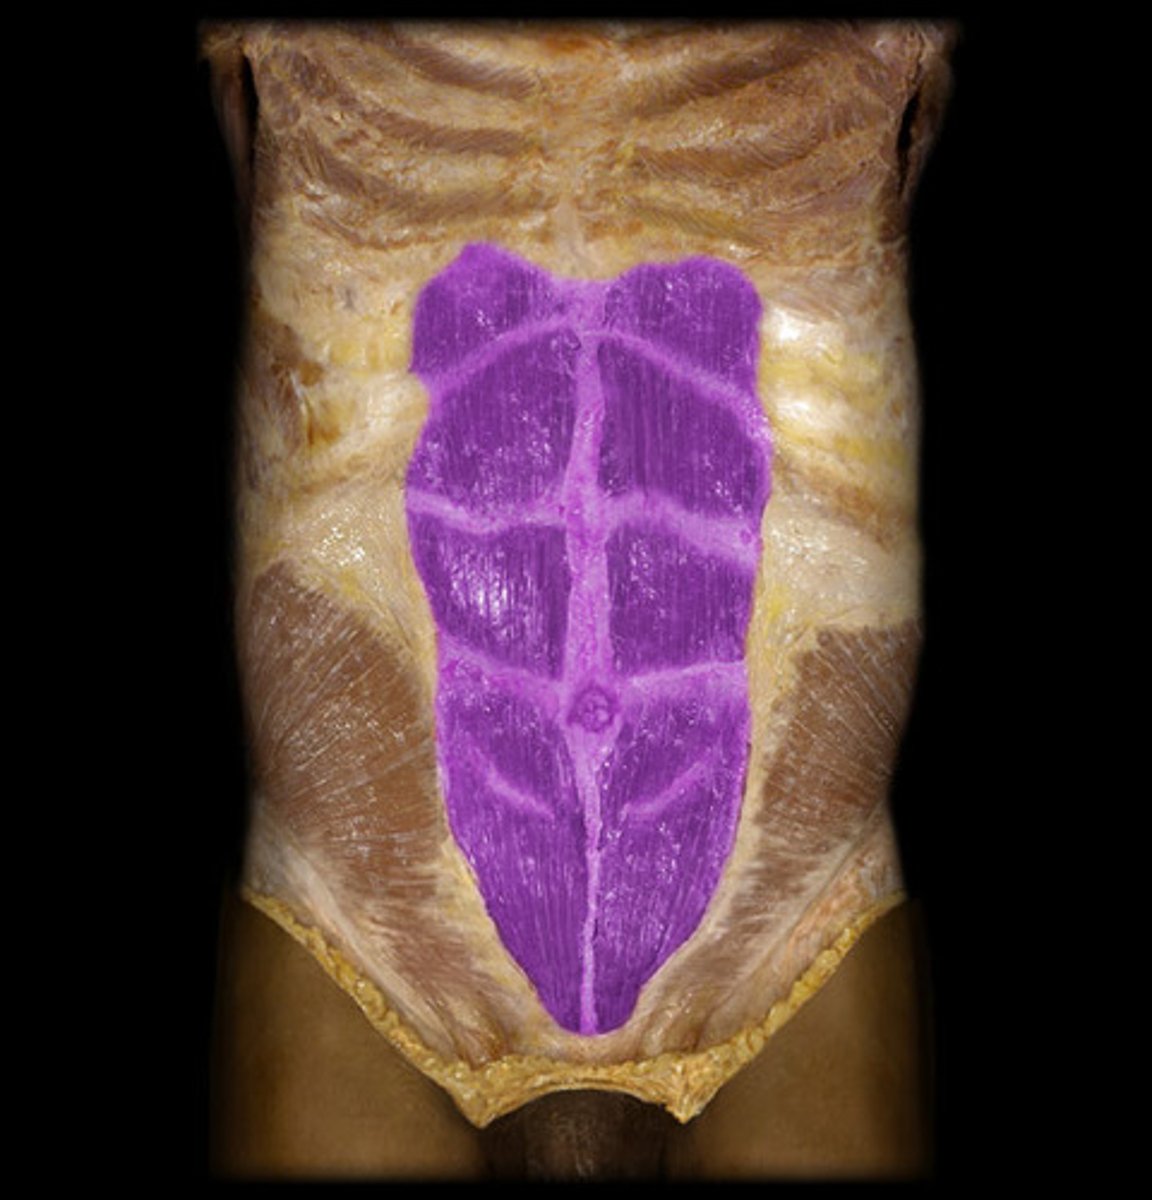

40

Rectus abdominis